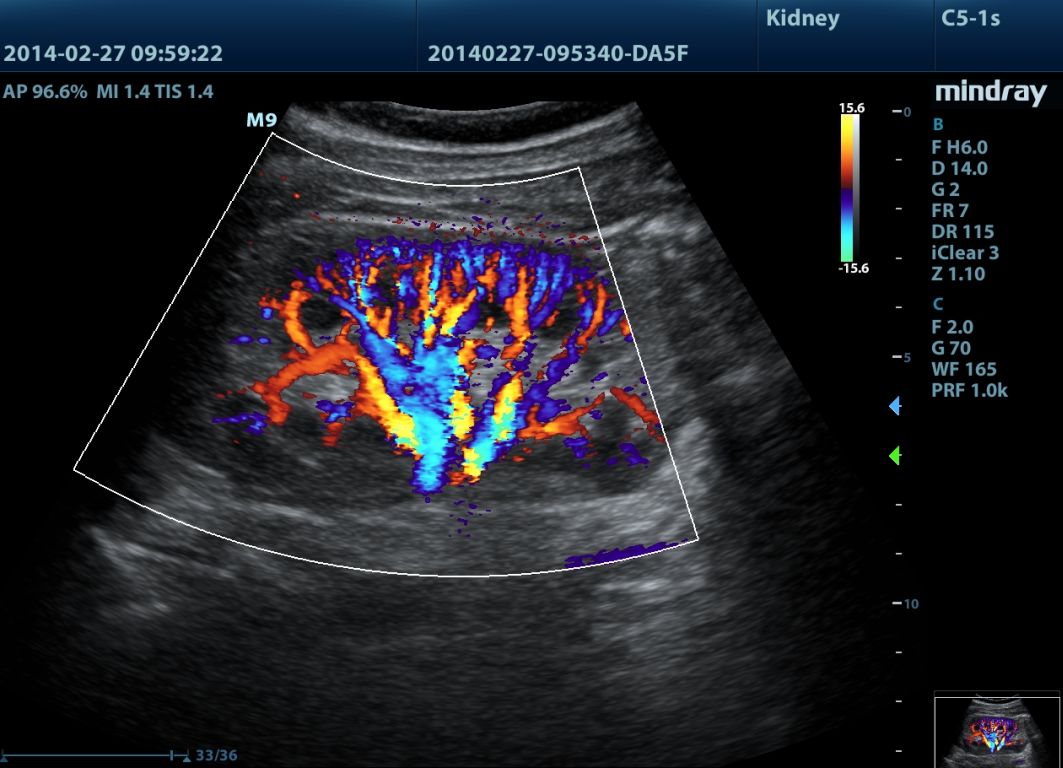

Klinické obrázky:

- HR Flow (farebné dopplerovské zobrazenie ultra jemných prietokov - patent Mindray)